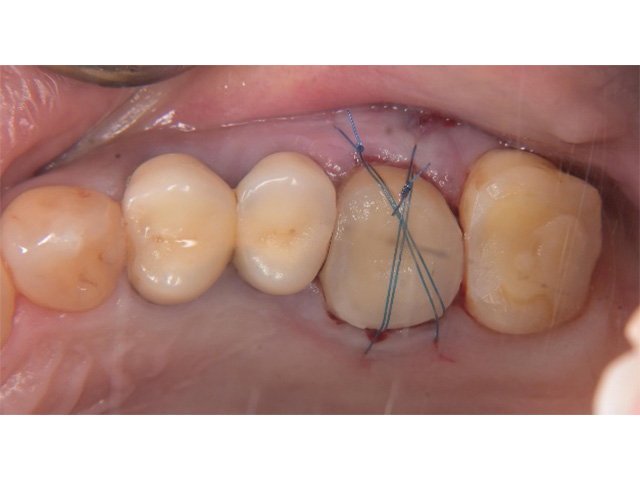

Before

親知らず移植後当日

After(移植後2か月)

After(移植後2か月)2

| 主訴 | 左下の奥歯がズキズキ痛む |

|---|---|

| 治療内容 | 左下第一大臼歯抜歯し左下智歯(親知らず)移植後の根管治療 |

| 治療回数・期間 | 7回(3か月)※根管治療は2回 |

| 費用 | 保険適応 |

| リスク・副作用 | 根管治療は術前の精密な診査診断および無菌環境下での治療によって成功率は高まってきましたが治療の成否を決める多くの要素があるため、根管治療がなされた後も再治療や外科処置、抜歯となる可能性が少なからずあります。また治療中には器具の破折や穿孔、修復物の損傷、歯の破折、術中・術後の痛みや腫れが生じることが稀にあります。根尖病変(再感染)を防ぐには適合の良好な補綴物を作製することや定期的なかみ合わせのチェックが必要です。 |